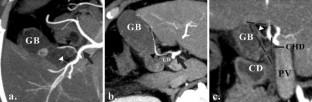

Assessment and classification of cystic arteries with 64-detector row computed tomography before laparoscopic cholecystectomy

Major complications of laparoscopic cholecystectomy are bleeding and bile duct injury, and it is necessary to clearly identify structures endoscopically to keep bleeding and injury from occurring. The aim of this study was to depict the anatomical variation between cystic arteries among patients using 64-detector row spiral computed tomography (CT) prior to laparoscopic cholecystectomy.

A total of 78 patients (31 men, 47 women) who underwent cholecystectomy were examined preoperatively using 64-detector row spiral CT between April 2012 and June 2013. The origin and number of cystic arteries and their relationship with the Calot triangle was evaluated by two independent observers. CT images were compared with laparoscopic cholecystectomy results.

The cystic arteries were delineated by CT in 73 of the 78 patients. The relationship between the cystic arteries and the Calot triangle was identified in 71 of the 78 patients. One cystic artery was found in 53 (73 %) of the 73 patients, while two cystic arteries were found in 20 (27 %) of the patients. A total of 55 (60 %) of the 91 cystic arteries passed through the Calot triangle. The remaining 36 cystic arteries (40 %) passed anterior, posterior, or inferior to the cystic duct. The relationship between the cystic arteries and the Calot triangle detected by CT was in agreement with the surgical records for all patients.

The configuration of the cystic arteries and their relationship with the Calot triangle can be identified using 64-detector row CT before laparoscopic cholecystectomy.

Fig. 3